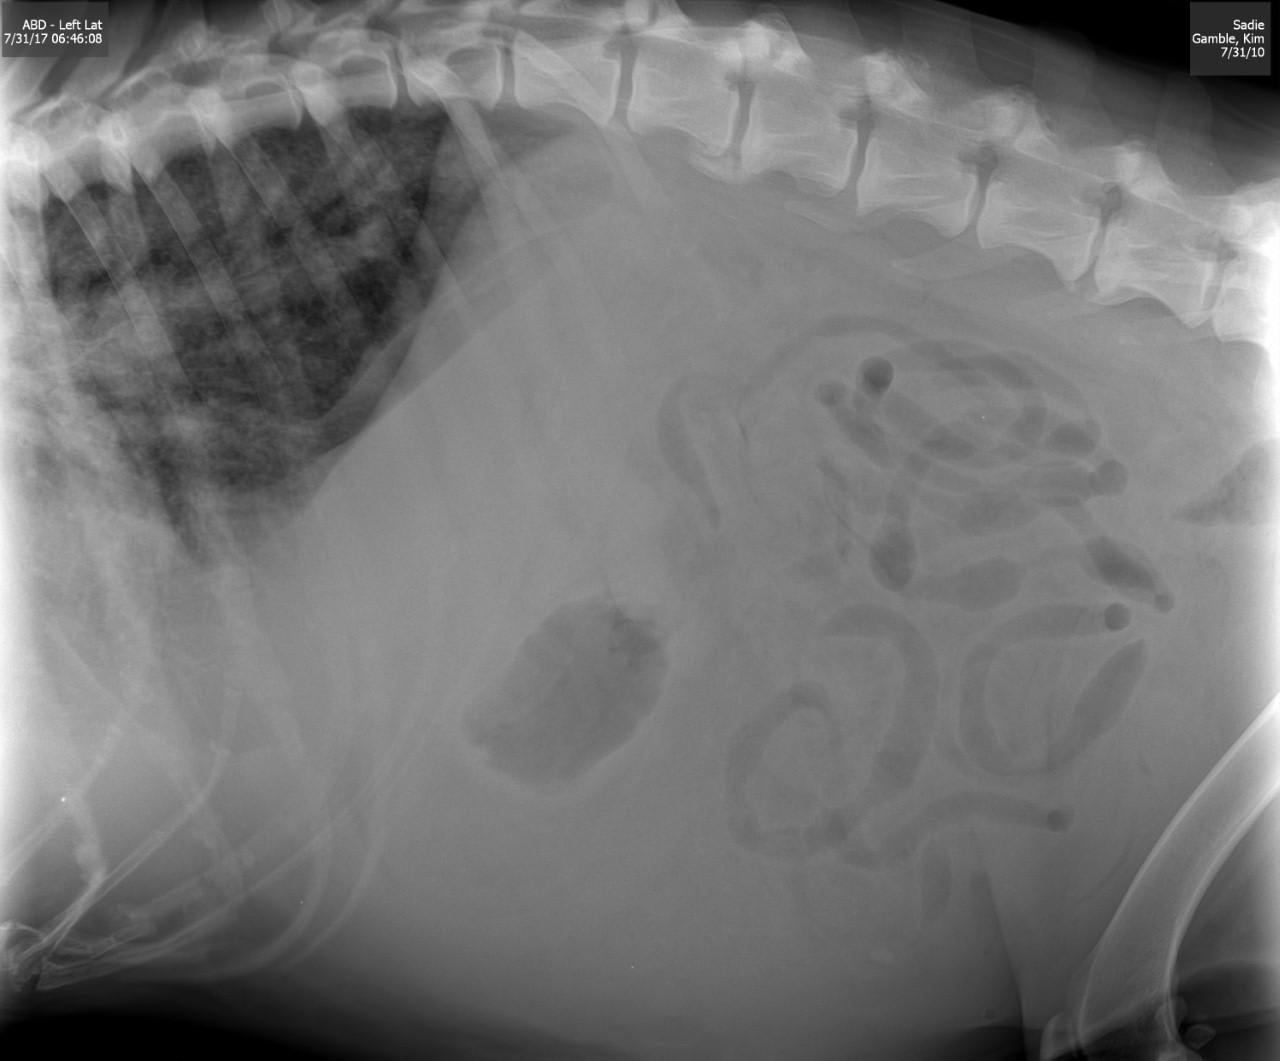

Pet's info: Dog | German Shepherd | Female | spayed | 7 years and 10 months old | 85 lbs

7 YR OLD GERMAN SHEPHARD, FLUID IN BELLY, HEAVY PAINTING, RAPID HEARTBEAT,STILL EATS, NO POOP, NO VOMIT, VET SAID SHES DYING SOON, BUT NO BLOODWORK WAS DONE AND GIVEN PREDNISOLONE & CLAVAMOX. HE SAID MAYBE CANCER, OR HEART, OR CIRVO SHES GETTING WORSE STILL HAVE NO ANSWER TO WHAT IS THE MATTER TO START TRYING TO HELP HER

Hi and thanks for using Petco Pet Education Center, formerly Petcoach! I'm so sorry to hear about Sadie. This sounds very serious. Anytime there is fluid in a body cavity, the situation is serious. I would need to know more to give a better answer but in a German Shepherd dog of this age, one thing is likely and that is a tumor of the spleen. These are called hemangioma or hemangiosarcoma or it could even be a hematoma or benign growth on the spleen that is bleeding. These are usually a surgical emergency especially if they are bleeding into the abdomen. Depending on what type of Other reasons for fluid to accumulate in the belly would be heart disease, liver disease, other tumors or masses in the abdomen, kidney problems. A tap of the abdomen (abdominocentesis) would reveal what the fluid is and maybe how to proceed. I would advise taking Sadie back to your vet or taking her somewhere else for a second opinion if you want to try to do something with her. And I would advise this as soon as you can get her there. Not sure if surgery is an option and that would depend on her condition and what you do comfortably afford for her. I'm so sorry again and I really hope that she gets better very soon.